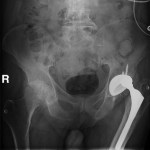

Hardware Complication – Dislocated left hip replacement hardware

Diagnosis: Dislocated left hip - hardware complication

Hardware Complication with Left Hip Dislocation

Diagnosis: Dislocated left hip due to hardware complication